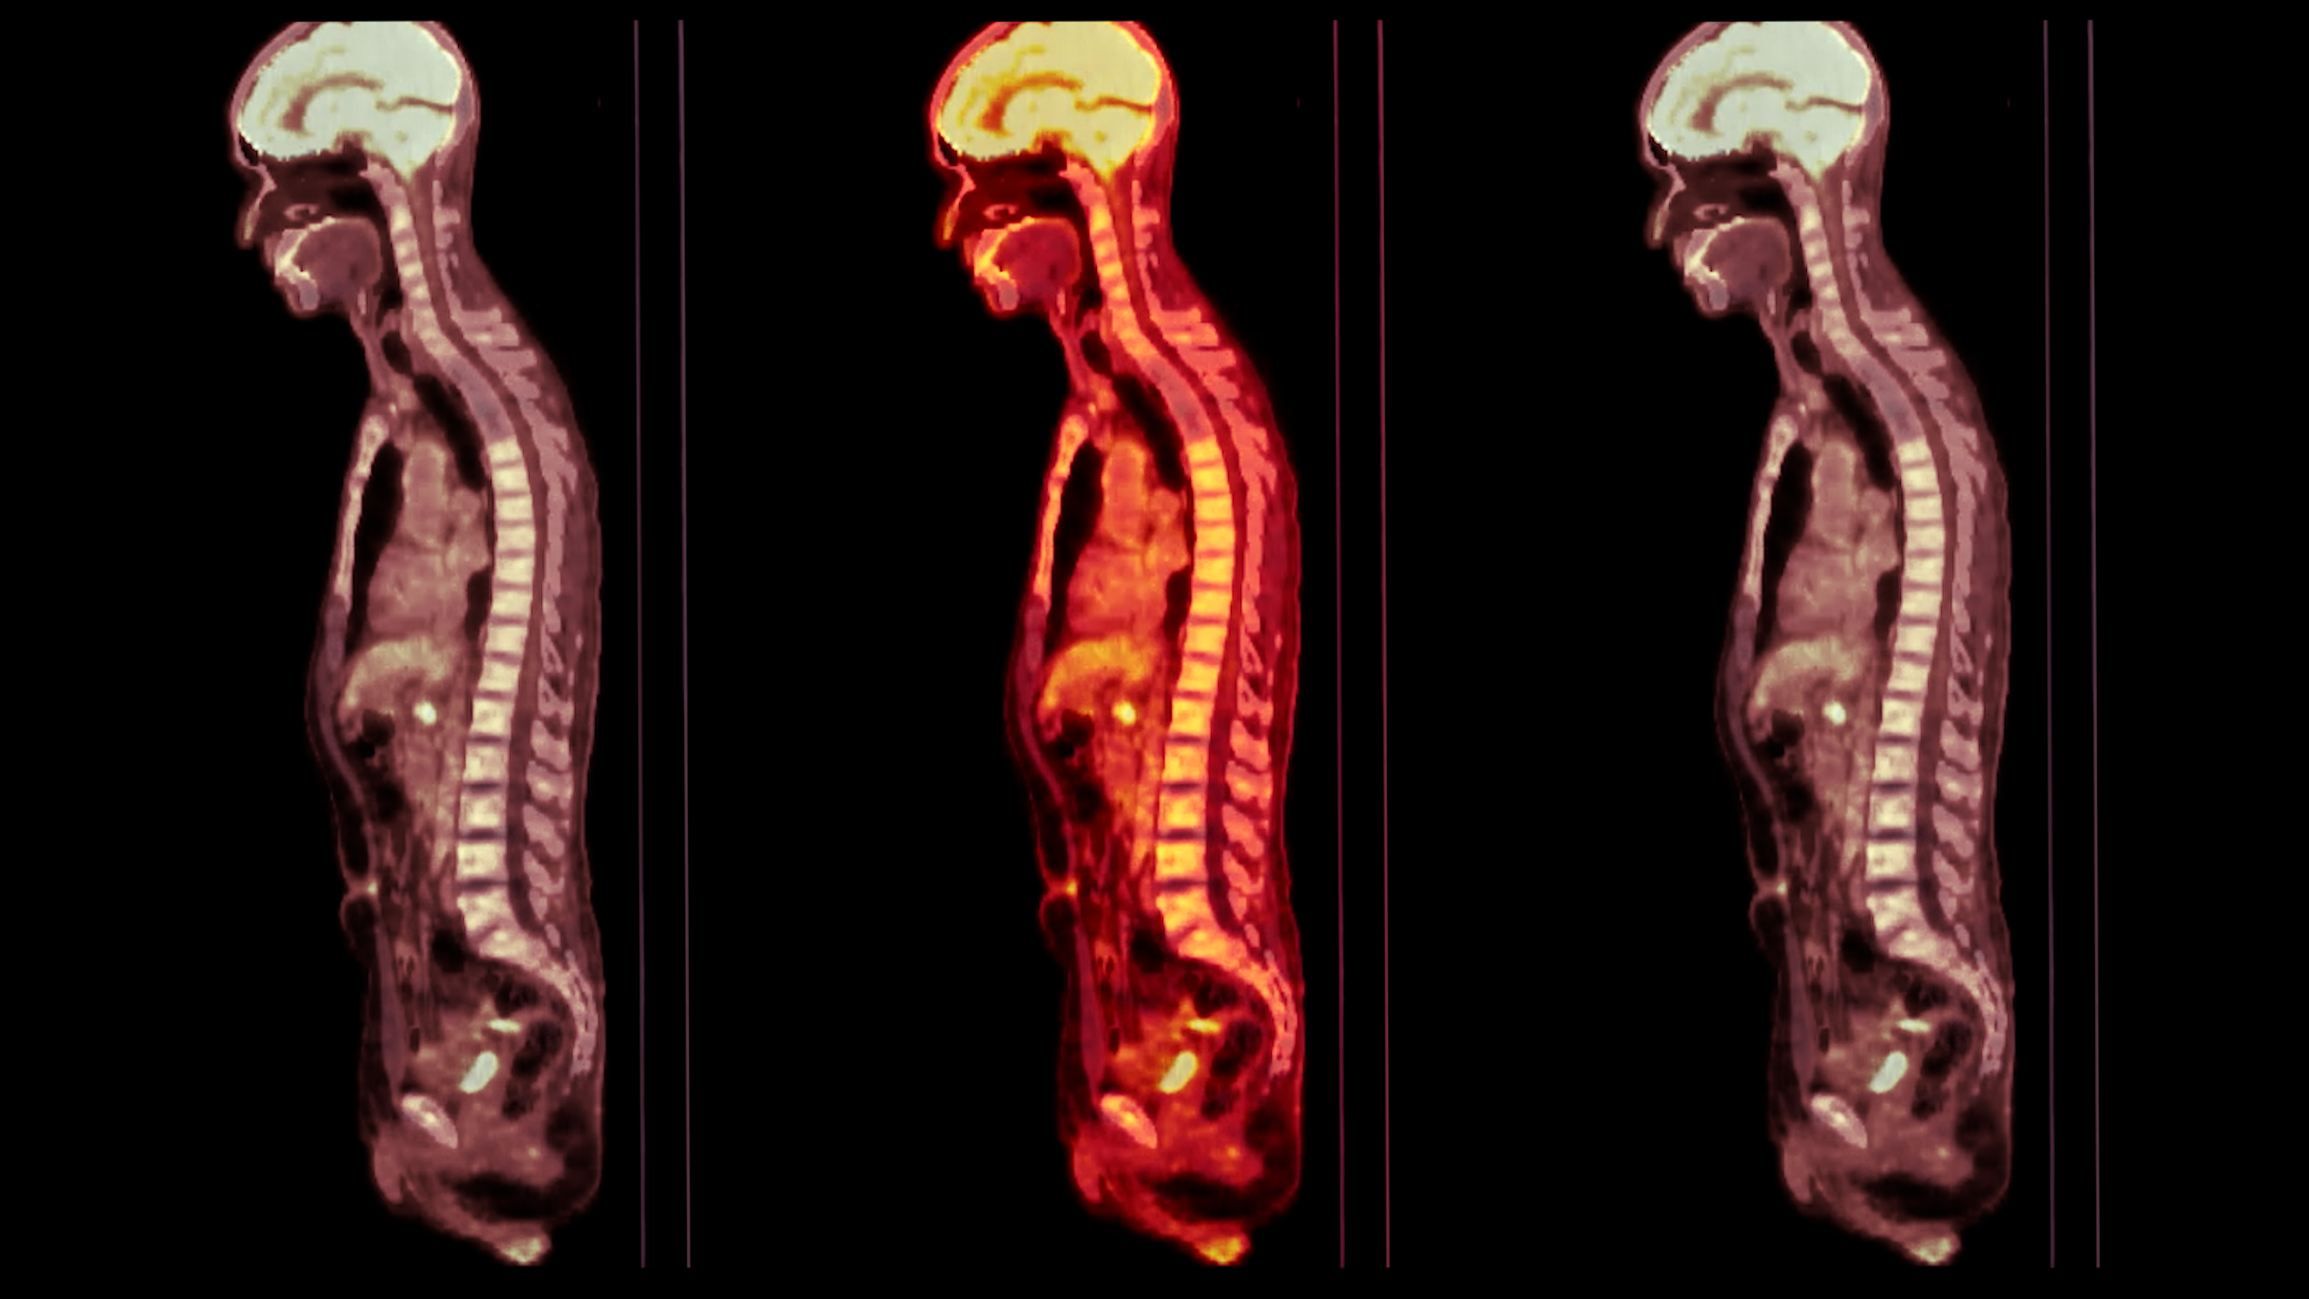

Positron Emission Tomography (PET) imaging is a revolutionary medical modality technique that has transformed the way diseases, particularly cancers, neurological disorders, and cardiac conditions, are diagnosed and treated. Unlike traditional imaging methods such as X-rays or MRI, PET scans provide a dynamic picture of what’s happening inside the body at a molecular level. This detailed insight allows physicians to see how organs and tissues are functioning in real-time, making it an invaluable tool in modern medicine.

PET imaging is based on the detection of gamma rays emitted from a radioactive substance administered to the patient. This substance, known as a radiotracer, is typically a biologically active molecule labelled with a radioactive isotope, such as glucose. The most commonly used tracer in PET imaging is fluorodeoxyglucose (FDG), a glucose analogue. When injected into the body, FDG travels through the bloodstream and accumulates in cells that use glucose for energy.

The mechanism of PET imaging hinges on the metabolic activity of cells. These cells in the body, particularly those growing rapidly, consume glucose as a source of energy. Cancer cells, for instance, are known to metabolise glucose much faster than normal cells. When FDG is injected, it gets taken up by these active cells, but unlike normal glucose, it does not undergo further metabolism. This accumulation of FDG makes rapidly growing cells, like cancer cells, visible on a PET scan.

When the FDG decays, it emits positrons, the antimatter counterparts of electrons. Upon encountering electrons, these positrons undergo annihilation, leading to the emission of gamma rays. The PET scanner then detects these rays, which circle around the patient, capturing images from multiple angles. A computer then reconstructs these images into detailed, three-dimensional representations of the patient’s internal metabolic processes.